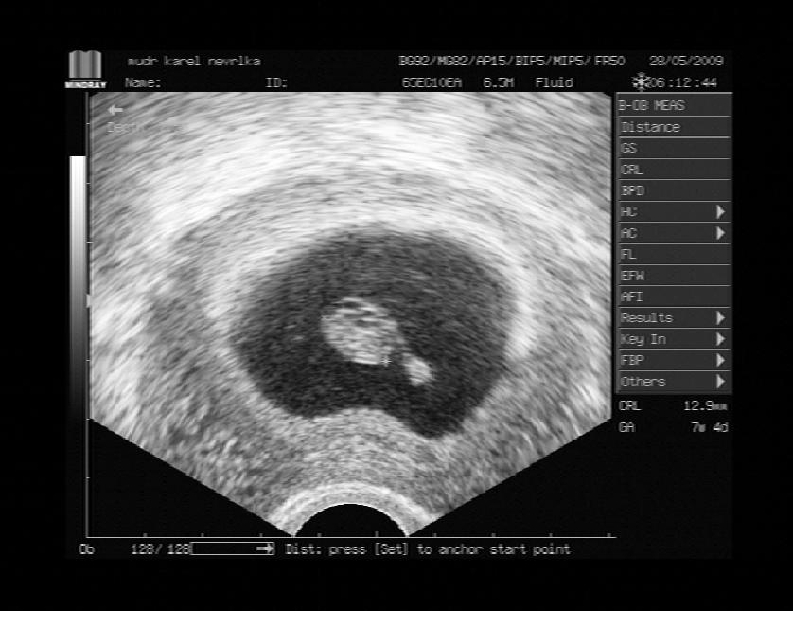

7tt+4